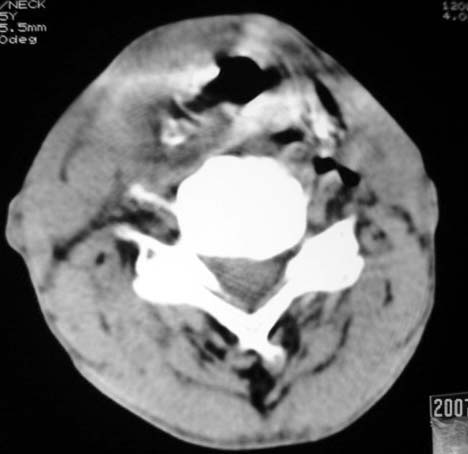

以下是引用dyqct在2007-4-20 16:19:00的发言:[br]考虑:1、左侧梨状窝区破裂伴左颈深、浅部气肿。[br] 2、右侧甲状腺区血肿(请追问病史是否伤及右颈部)。[br] 3、建议病情稳定后增强扫描除外右侧甲状腺腺瘤。